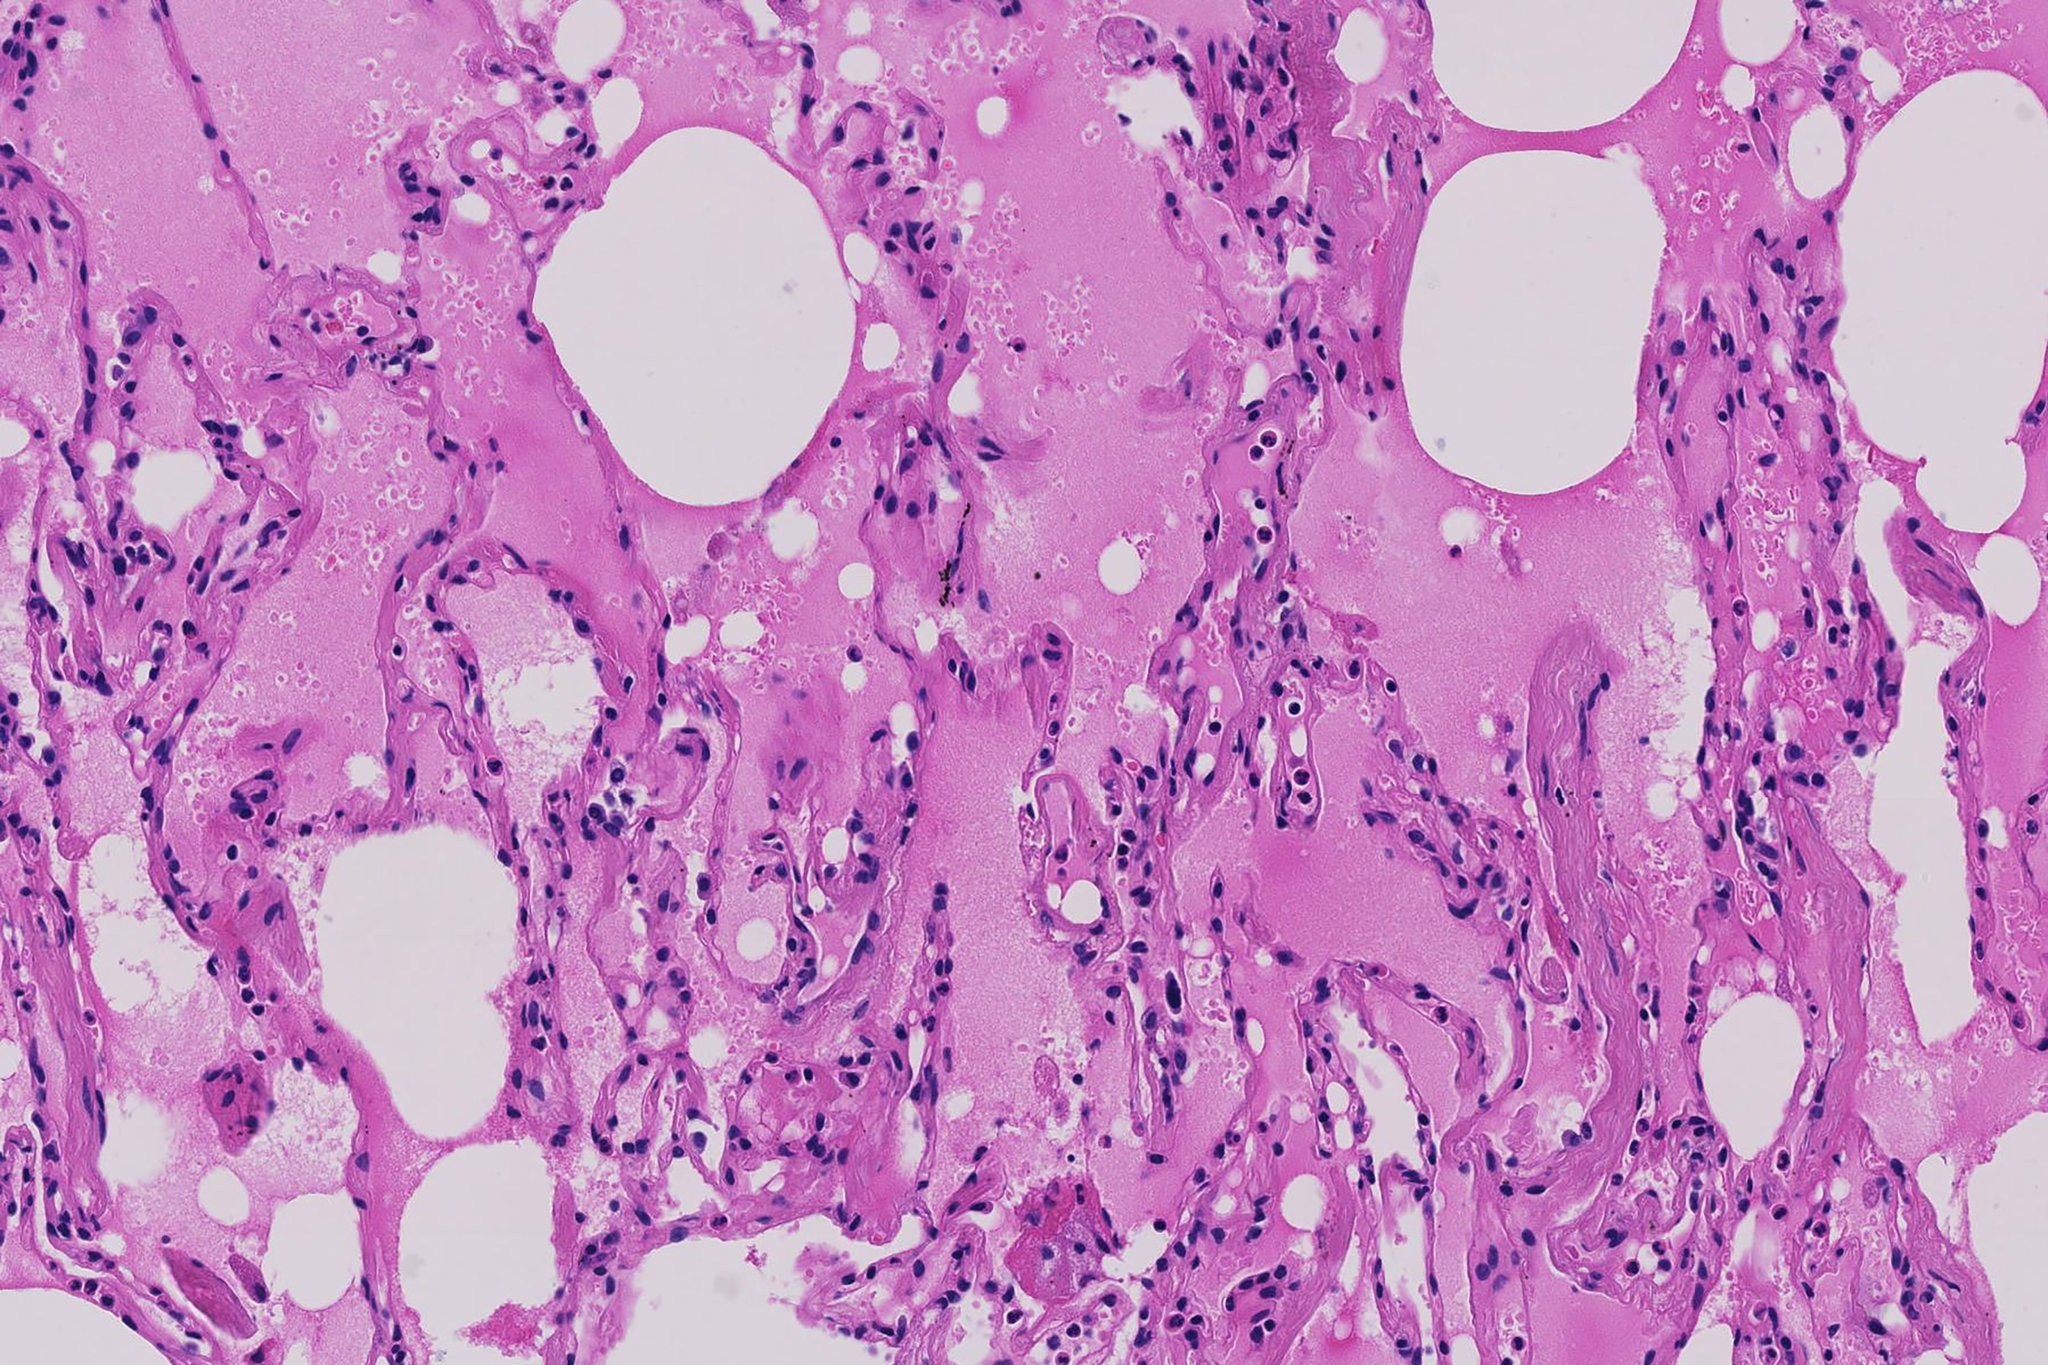

virus corona anh 2

Ảnh chụp tuyến phổi của bệnh nhân đến từ Vũ Hán, cho thấy phế nang chứa đầy chất lỏng màu hồng, sự thay đổi sớm nhất trong phổi của bệnh nhân. Ảnh: Shu-Yuan Xiao.

Sự sưng tấy và dòng lưu thông oxy bị suy yếu có thể khiến những khu vực đó trong phổi chứa đầy chất lỏng, mủ và tế bào chết. Viêm phổi, một dạng nhiễm trùng, có thể xảy ra.